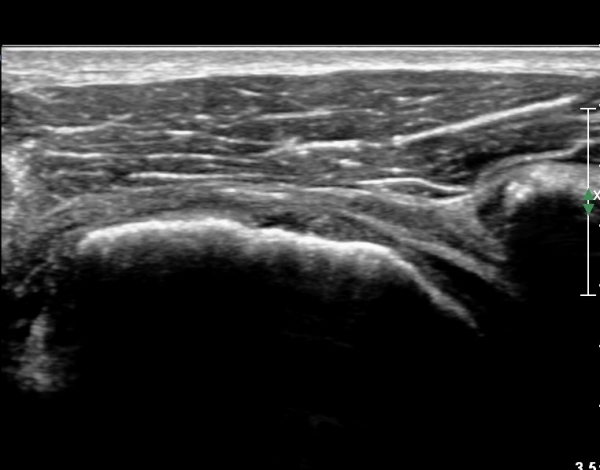

ÆÈÀ» ¿ÜȸÀüÇϸ鼭 °üÂûÇÏ´Ï °ß°©ÇÏ±Ù°Ç ÆÄ¿­ÀÌ ¶Ñ·ÈÇÔ(»çÁø 2, 3).

°ß°©ÇÏ±Ù°Ç »óºÎ Á¾´Ü¸é°Ë»ç¿¡¼­ °ß°©ÇϱٰǠ ÆÄ¿­ÀÌ ¶Ñ·ÈÇÔ(»çÁø 4, 5).